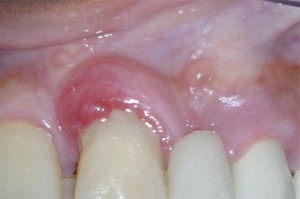

perio abscess

Periodontal abscess due to bacteria in the gums due to plaque and calculus